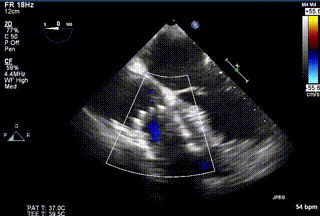

2021年12月24日,復(fù)旦大學(xué)附屬中山醫(yī)院葛均波院士團(tuán)隊(duì)成功應(yīng)用LuX-Valve Plus為一例極重度三尖瓣反流(TR)合并房顫、房缺的患者完成了經(jīng)血管三尖瓣置換術(shù),這是在前基礎(chǔ)上,本周完成的第三例經(jīng)血管三尖瓣置換手術(shù),葛均波院士、周達(dá)新教授等與心外科魏來教授、賴顥教授,心超室的潘翠珍教授、李偉教授及麻醉科的郭克芳教授共同完成了本周手術(shù),均獲得圓滿成功!患者術(shù)后超聲顯示無TR,臨床癥狀明顯改善。本周手術(shù)的成功也為LuX-Valve Plus救治性臨床研究添上了濃墨重彩的一筆。

三例患者入院后,葛均波院士團(tuán)隊(duì)周達(dá)新教授、潘文志教授、張?jiān)床┦俊㈥惿┦考靶某业呐舜湔浣淌?、李偉教?/strong>對(duì)患者的情況進(jìn)行詳細(xì)評(píng)估和討論,最終決定為三例患者選擇LuX-Valve Plus40mm、50mm和50mm型號(hào)的瓣膜進(jìn)行手術(shù)治療。手術(shù)后即刻拔除氣管插管,術(shù)后患者三尖瓣反流癥狀得到顯著改善,復(fù)查心超結(jié)果顯示人工三尖瓣瓣膜支架固定穩(wěn)定,瓣葉關(guān)閉形態(tài)未見異常,未見明顯反流。